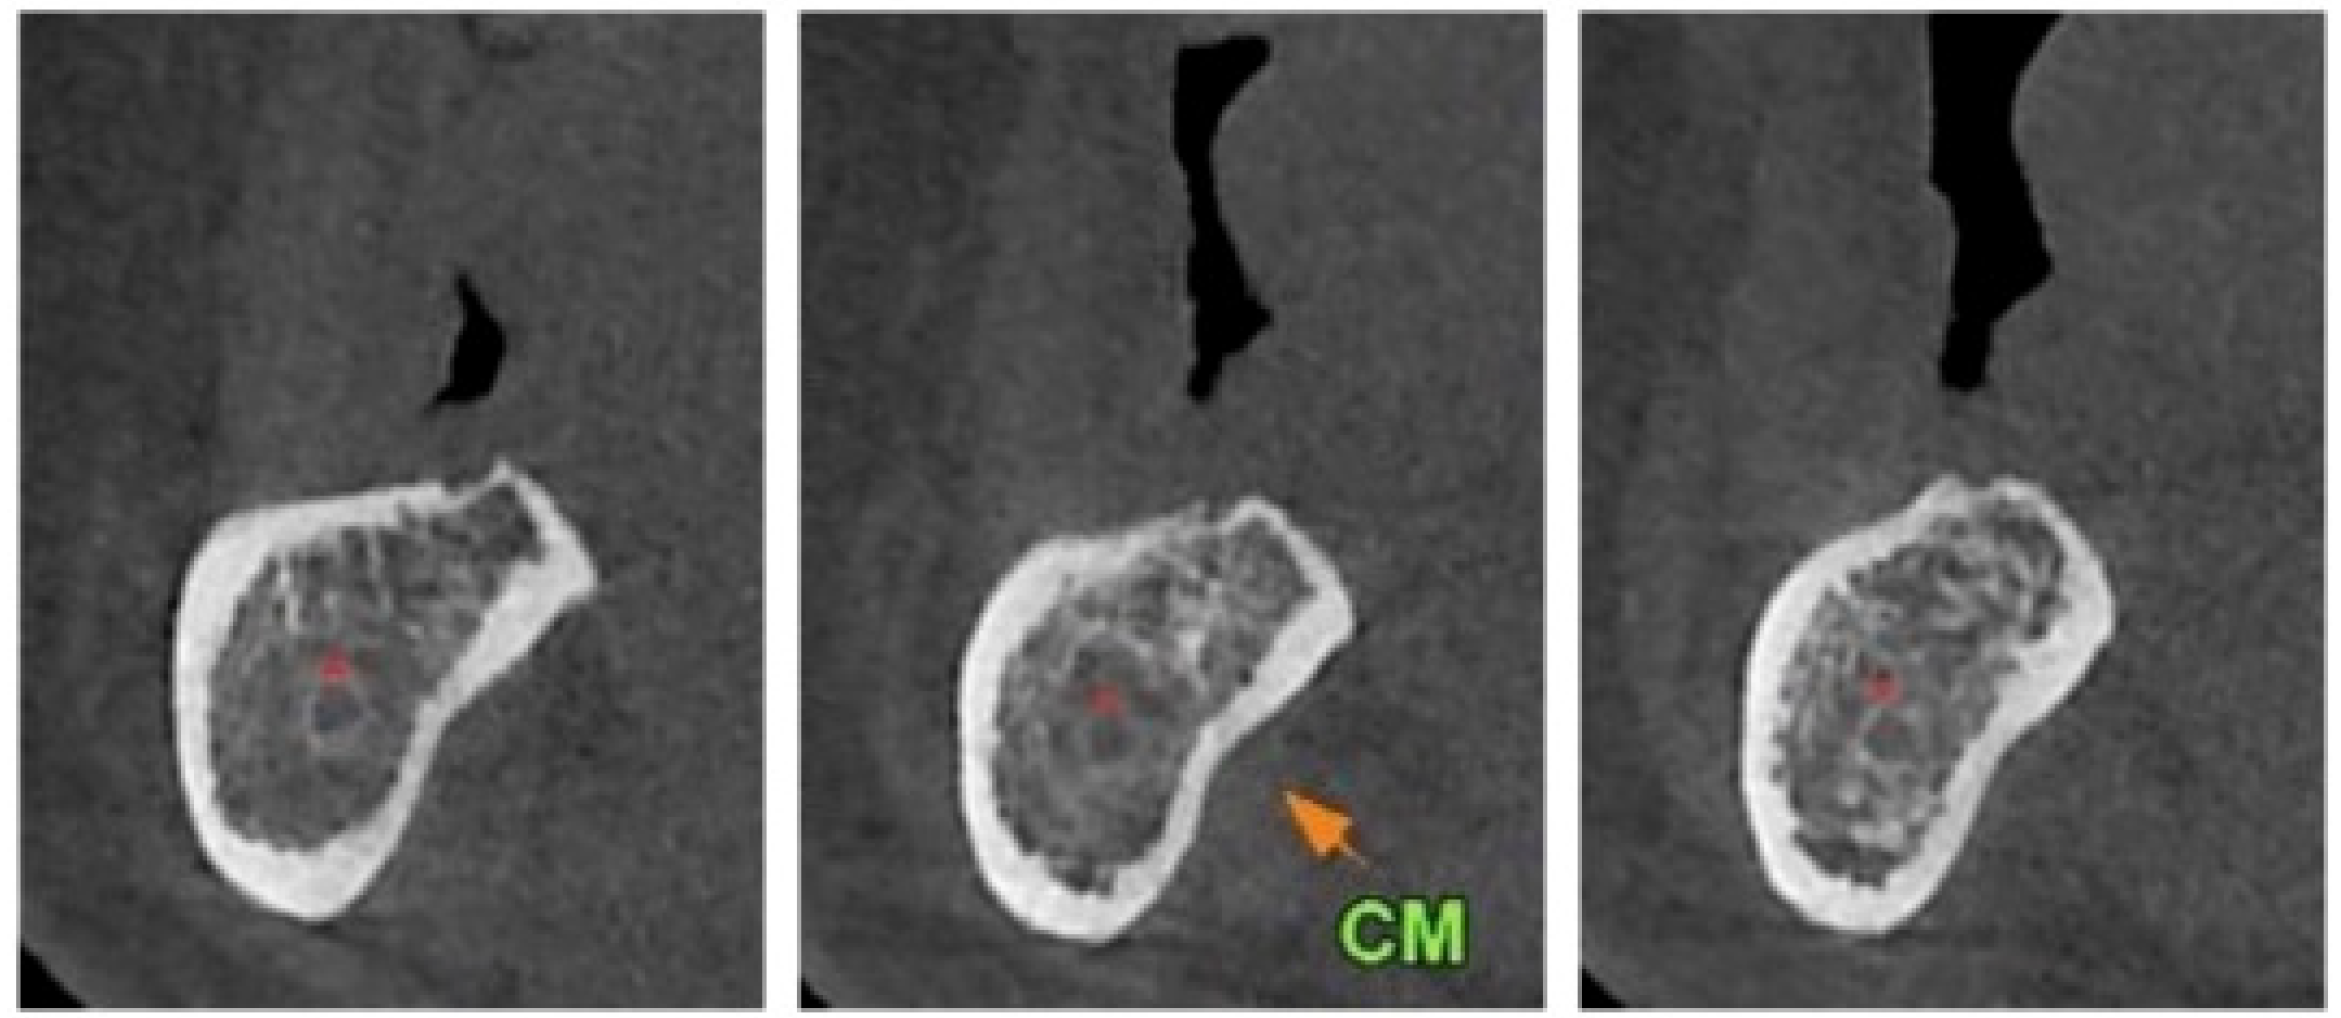

Dynamic Navigated “Sandwich” Technique: A Novel Surgical Approach for Safe Osteotomies in the Rehabilitation of an Atrophic Posterior Mandible: A Case Report

- Felice, P.; Barausse, C.; Pistilli, R.; Spinato, S.; Bernardello, F. Guided “Sandwich” Technique: A Novel Surgical Approach for Safe Osteotomies in the Treatment of Vertical Bone Defects in the Posterior Atrophic Mandible: A Case Report. Implant. Dent. 2014, 23, 738–744. [Google Scholar] [CrossRef]